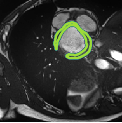

Despite their outstanding accuracy, semi-supervised segmentation methods based on deep neural networks can still yield predictions that are considered anatomically impossible by clinicians, for instance, containing holes or disconnected regions. To solve this problem, we present a Context-aware Virtual Adversarial Training (CaVAT) method for generating anatomically plausible segmentation. Unlike approaches focusing solely on accuracy, our method also considers complex topological constraints like connectivity which cannot be easily modeled in a differentiable loss function. We use adversarial training to generate examples violating the constraints, so the network can learn to avoid making such incorrect predictions on new examples, and employ the Reinforce algorithm to handle non-differentiable segmentation constraints. The proposed method offers a generic and efficient way to add any constraint on top of any segmentation network. Experiments on two clinically-relevant datasets show our method to produce segmentations that are both accurate and anatomically-plausible in terms of region connectivity.